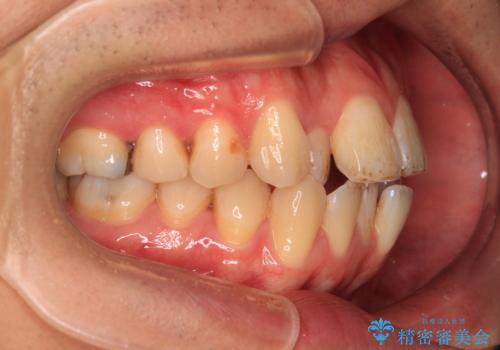

- 口元の突出感が強く、口が閉じにくいことを主訴として来院された患者さんの症例をご紹介します。

前歯部の叢生(デコボコ)も認められ、歯がきれいに並ぶためのスペースが不足している状態でした。

これらの問題を総合的に改善するため、上下左右の第一小臼歯を計4本抜歯し、スペースを確保する治療計画を立てました。